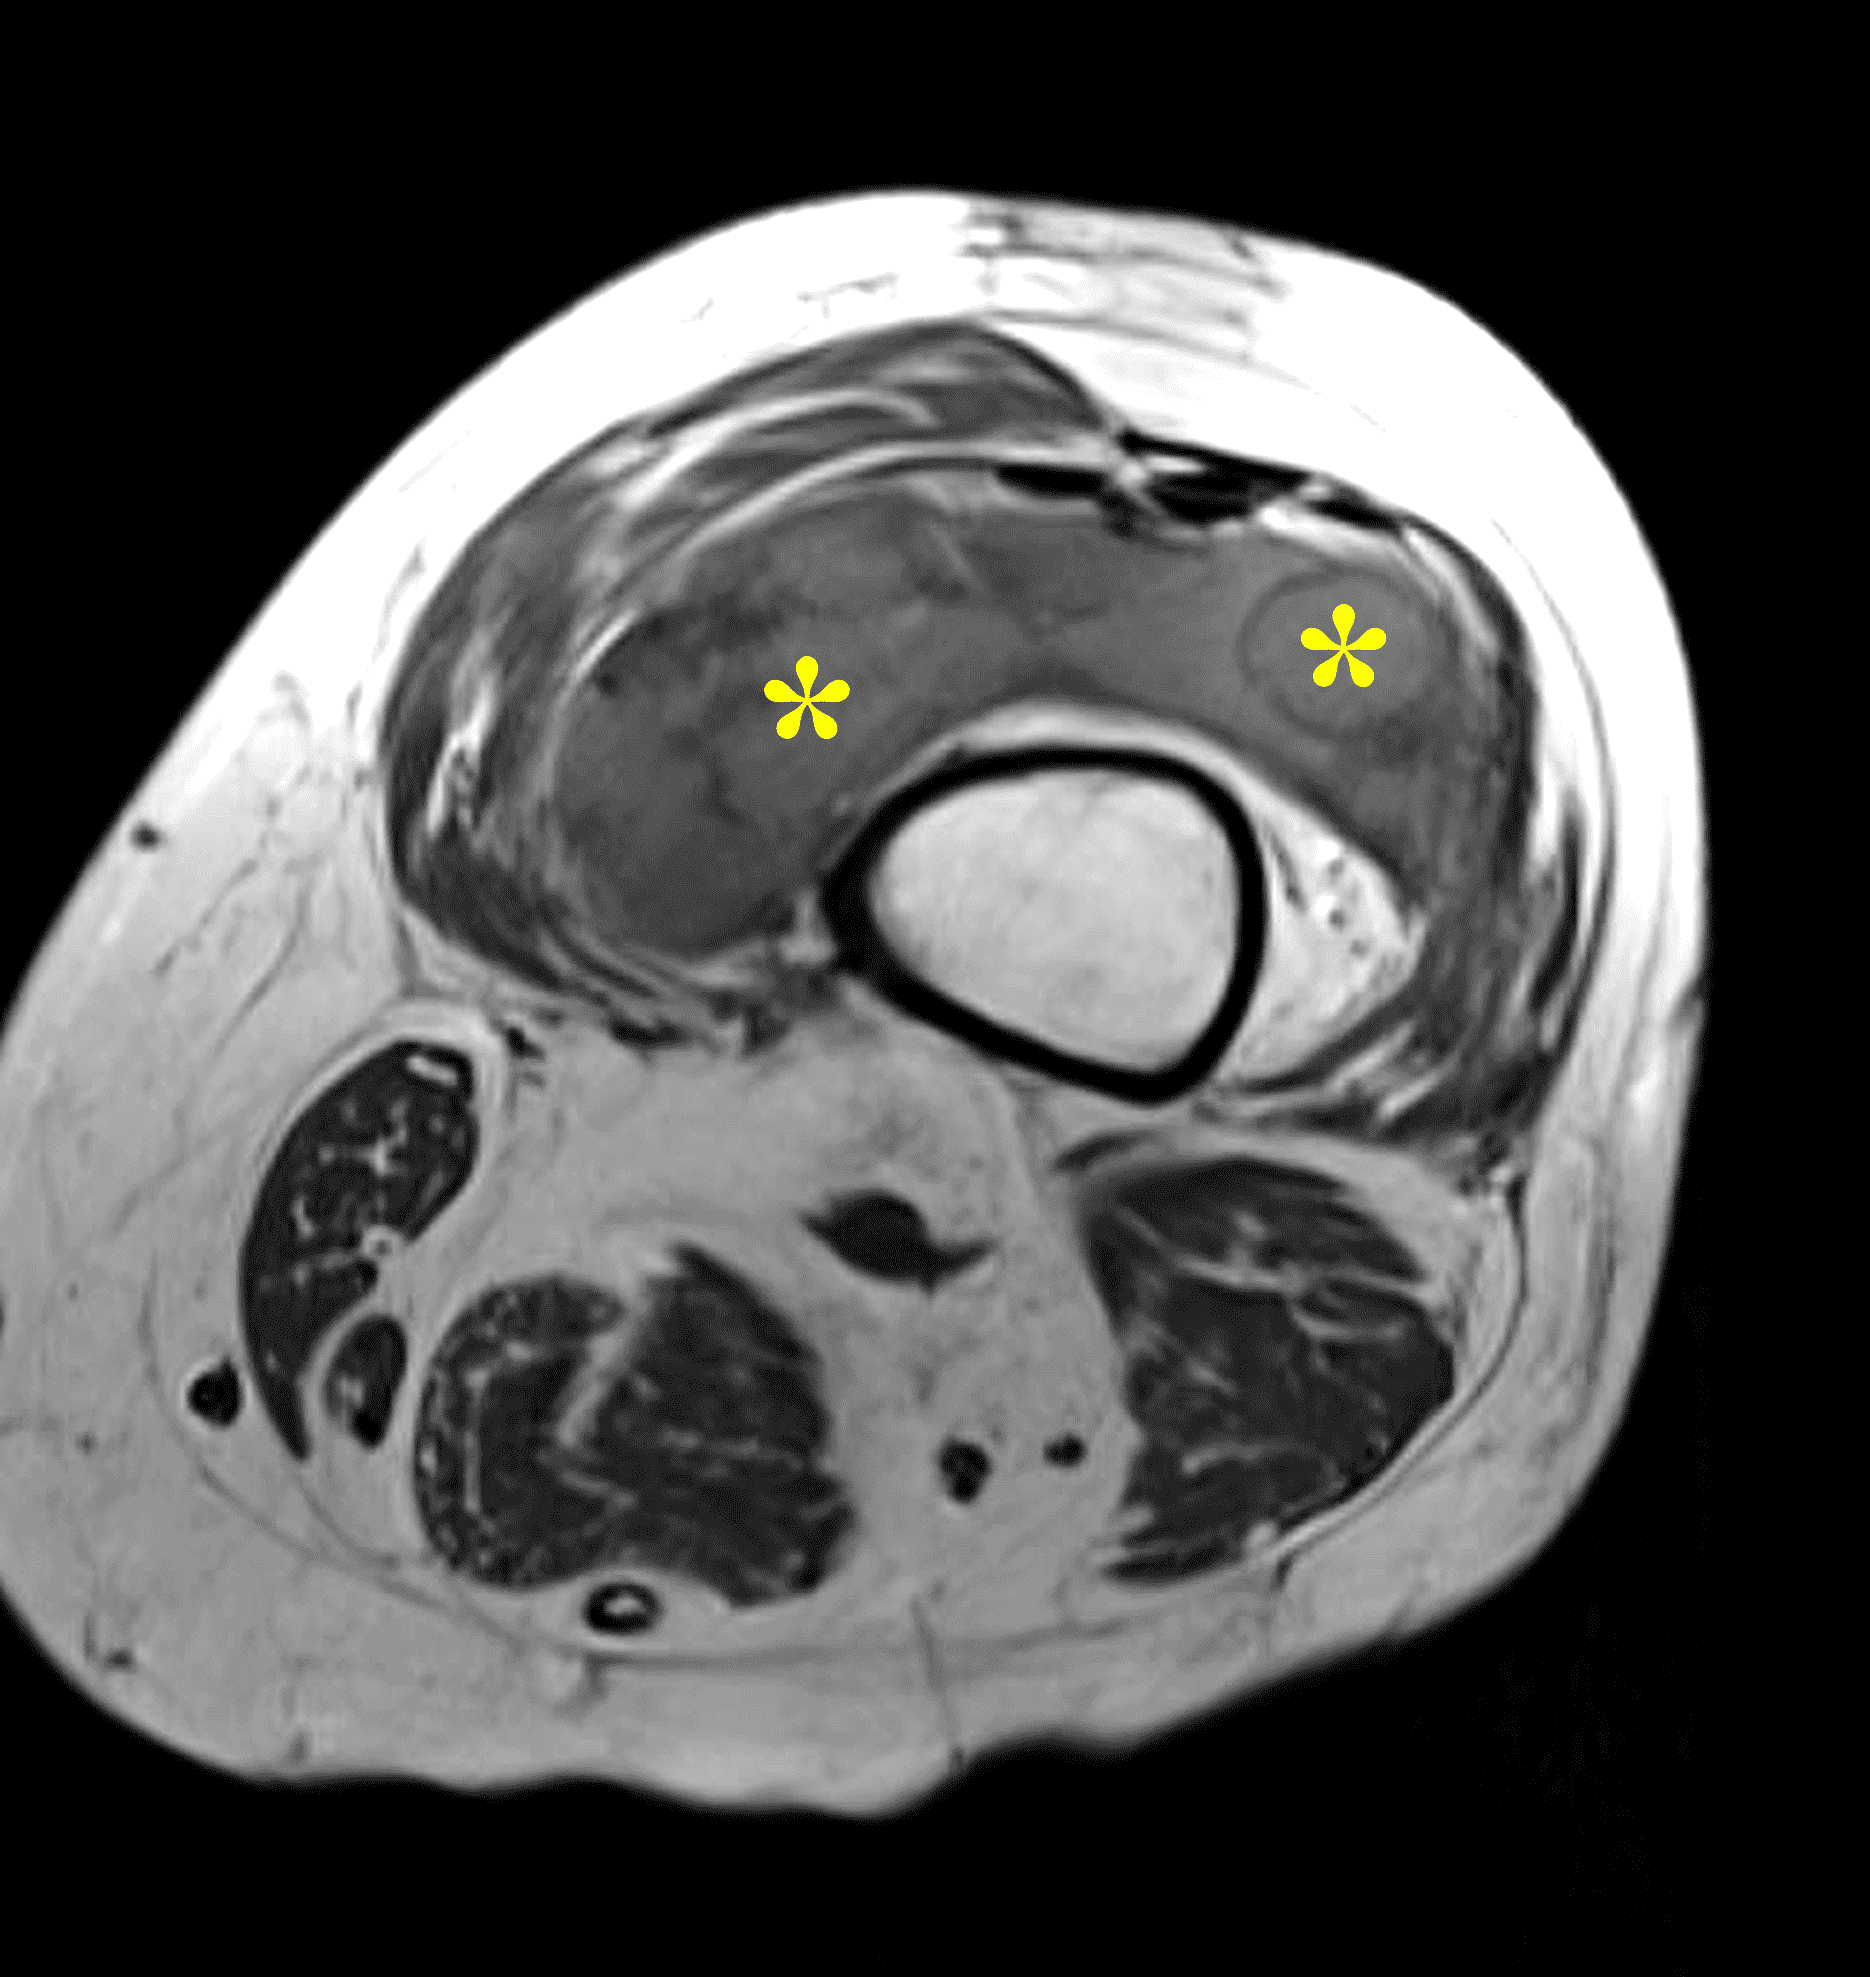

Figure 7: Synovial chondrosarcoma in the knee joint. Axial (7A) T1-weighted and (7B) fat-suppressed water-sensitive images show a multinodular, synovial mass (asterisks) in the suprapatellar recess, mildly hyperintense compared to skeletal muscle. This example shows no bone invasion or extra-articular spread, so diagnosis required histologic confirmation.